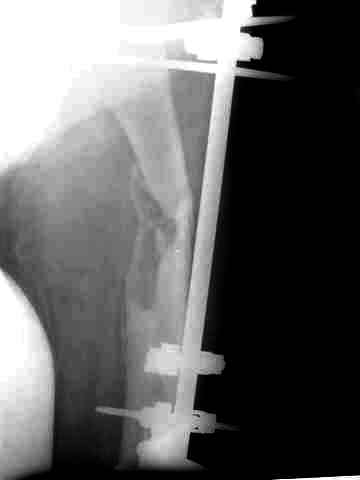

Этот стиль мне полностью приемлем и понятен. Наверно я бы поступил также. Но статистика упрямая вещь. Сколько у тебя или у другого врача опыта по замещению дефектов бедра? У меня за 25 лет работы 3, и еще около 15 случаев удлинения бедра. Случай у тебя очень сложный. Если Вы выбираете Илизаровскую методику то надо на в/з хорошую дугу, не менее 4-5 спиц с напайками.Стержни хороши когда кость не измучена и на 2-4 месяца. Здесь аппарат на 6-8 месяцев. Если есть желание я только за, и

желаю только успеха и чтоб все трудности которые будут преодолел.

Прикрепляю пример замещения дефекта бедра 20 см, после резекции по поводу опухоли, эндопротеза Сиваша, вялотекущего остеомиелита со свищами в течении 3 лет. Получилось хорошо и всего за 6 месяцев в аппарате. Колена не было. У Вас случай сложнее. Это было в 1998г. Я работал в ЦИТО и у меня было 4 больных, я занимался им с утра до ночи. Сейчас 60 больных и операций в нашем отделении 25-30 в неделю.Если могу чем помочь - нет проблем.